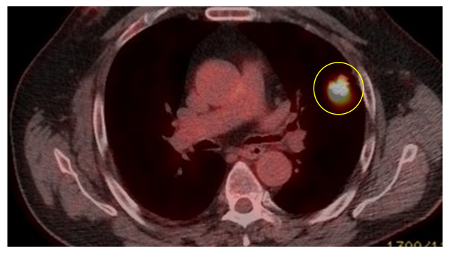

The Herder model (that incorporates F-18 fluorodeoxyglucose [FDG] avidity) has been found to be more accurate in patients who undergo positron emission tomography (PET-CT) evaluation of pulmonary nodule.[38][39] UK guidelines recommend that selected patients (pre-test probability of malignancy >10% and solid component of a nodule greater than the local threshold size [usually 8 to 10 mm]) are evaluated by PET-CT and that the Herder model is used to determine risk thereafter.[4][40]

[Figure caption and citation for the preceding image starts]: PET CT scan with 18-fluorodeoxyglucose (18-FDG) showing a low uptake in a semi-solid right upper lobe posterior lesion. Surgical resection confirmed adenocarcinoma with primarily lepidic patternFrom the collection of Dr George Tsaknis, MD, PhD, FRCP(London), MRQA, MAcadMEd, PGCert; used with permission [Citation ends].

[Figure caption and citation for the preceding image starts]: PET CT scan with 18-fluorodeoxyglucose (18-FDG) showing a high uptake peripheral left lung lesion. Surgical resection confirmed a moderately differentiated squamous cell lung cancerFrom the collection of Dr George Tsaknis, MD, PhD, FRCP(London), MRQA, MAcadMEd, PGCert; used with permission [Citation ends].